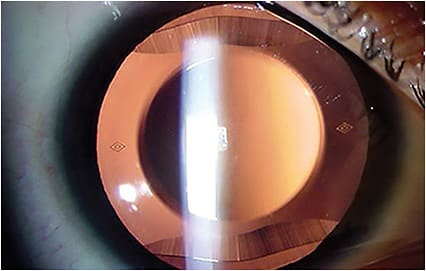

AS-OCT images depicting adequate vaults (250 μm and 740 μm, respectively) of an ICL over the natural crystalline lens. IMAGE COURTESY KATHRYN HATCH, MD - Accurate anterior chamber depth measurement. This can be measured using biometry, Scheimpflug photography, AS-OCT, or partial coherence interferometry.8 Many biometers measure anterior chamber depth from the corneal surface to the lens, rather than from the endothelium to the lens, so the central corneal thickness must be subtracted from the measurement to arrive at an accurate measurement.

- Prevention of pupillary block with the Visian ICL. Two large peripheral iridotomies, typically made at 10 o’clock and 2 o’clock, should be made preoperatively or intraoperatively to prevent pupillary block. Additionally, careful note should be taken of ideal ICL vault, typically measured relative to corneal thickness. Optimal vault is 0.75 to 1.5 corneal thickness on slit lamp examination, approximately 250 μm to 750 μm.10